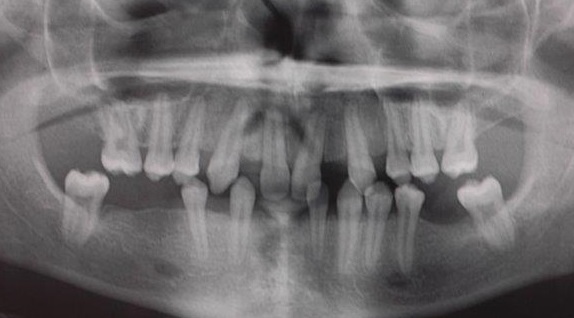

Orthopantomogramme